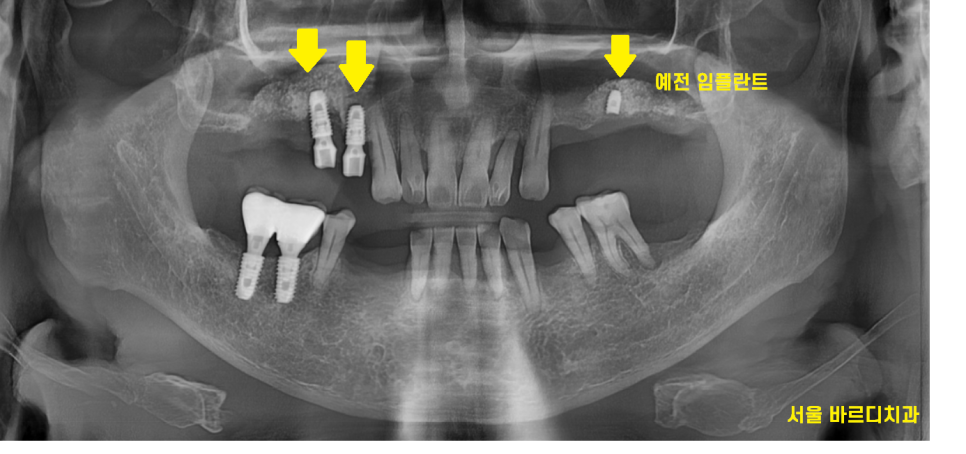

23.12.16

병원을 처음 방문하셨을때부터

이미 심어둔 임플란트가 있었습니다.

23.02.20

ct를 통해 분석을 해보니

예전에 식립한 임플란트 3개 중

1개는 그대로 쓰셔도 되었습니다.

식립한지 몇년 지났지만

문제가 없어서 기존 임플란트를 활용

나머지 부분에 대해서만

임플란트 재수술 하기로 결정하였습니다.